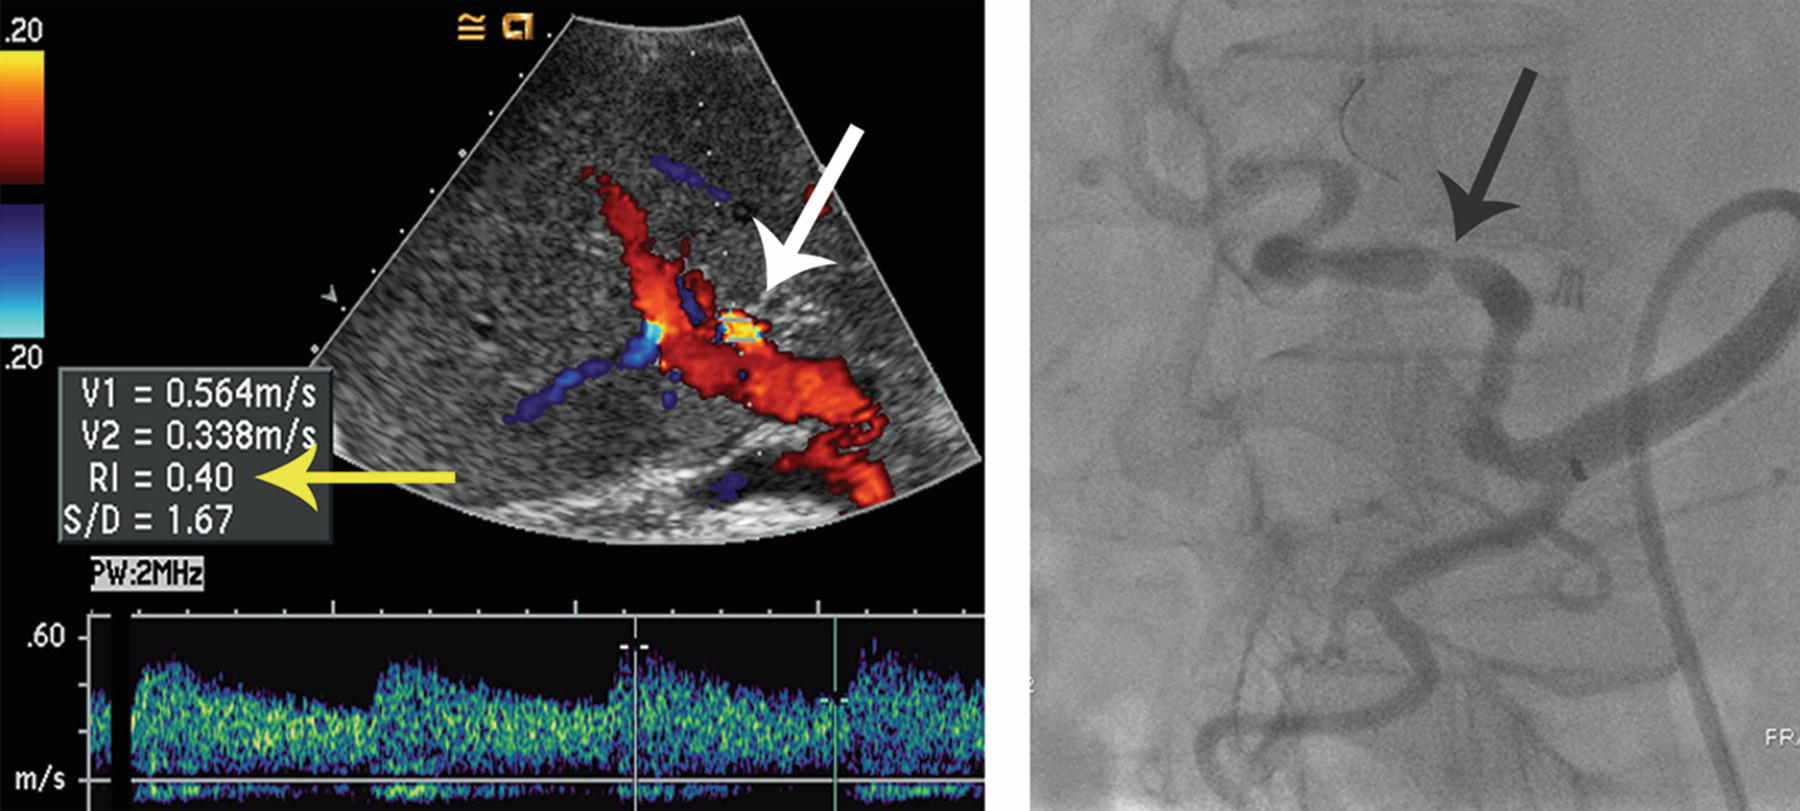

45 A patient with a liver transplant was evaluated with ultrasound followed by angiography. The arrow indicates the location of spectral Doppler interrogation. What vascular complication is demonstrated?

A. Hepatic artery stenosis

B. Portal vein thrombosis

C. Pseudoaneurysm

D. Arterioportal fistula